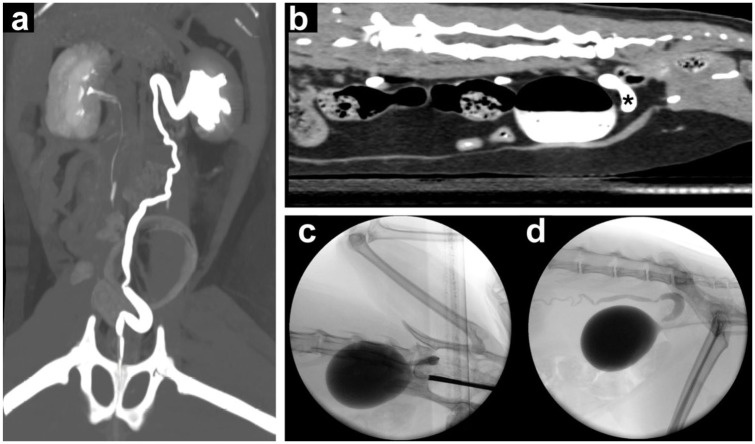

本研究的目的是报告4只母猫的临床表现、诊断评价和输尿管异位治疗结果。回顾了2016年至2021年间诊断为输尿管异位的猫的医疗记录。如果猫被确诊为外输尿管(3例)或内输尿管(1例)异位,并接受了膀胱内端侧神经输尿管造口术或膀胱镜下激光消融术的手术矫正。从医疗记录中获得的信息包括病史、信号、临床病理数据、影像学结果、治疗情况、术后并发症和长期临床随访。4只患有单侧异位输尿管的母猫均出现尿失禁(4/4),其中一半(2/4)还出现复发性尿路感染。治疗前诊断为外壁异位输尿管3例,内壁异位输尿管1例。相关性和新信息对三只外壁异位输尿管猫行膀胱内神经输尿管端侧造口术,对外壁异位输尿管猫行膀胱镜激光消融术。长期随访显示,异位输尿管治疗后无尿失禁复发或下尿路体征(中位随访1705天)。本研究表明,膀胱内输尿管端侧神经输尿管端侧造口术和膀胱镜下激光消融术是治疗猫单侧输尿管异位的有效且安全的长期治疗选择。

Case series summaryThe objective of this study was to report the clinical presentation, diagnostic evaluation and outcome of ectopic ureter treatment in four female cats. Medical records of cats diagnosed with ectopic ureter between 2016 and 2021 were reviewed. Cats were included if they had a confirmed diagnosis of an extramural (three cases) or intramural (one case) ectopic ureter and underwent either surgical correction using an intravesicular end-to-side neoureterocystostomy technique or cystoscopic laser ablation. Information obtained from the medical records included history, signalment, clinicopathological data, imaging findings, treatment performed, postoperative complications and long-term clinical follow-up. Four female cats with unilateral ectopic ureters were identified, all of which (4/4) presented with urinary incontinence, with half (2/4) also having recurrent urinary tract infections. Pre-treatment diagnostics revealed three cases of extramural and one case of intramural ectopic ureters.Relevance and novel informationSurgical correction was performed using intravesicular end-to-side neoureterocystostomy for the three cats with an extramural ectopic ureter and cystoscopic laser ablation for the cat with an intramural ectopic ureter. Long-term follow-up showed no recurrence of urinary incontinence or of lower urinary tract signs after ectopic ureter treatment (median follow-up 1705 days). This study demonstrates that both intravesicular end-to-side neoureterocystostomy and cystoscopic laser ablation are effective and safe long-term treatment options for cats with unilateral ectopic ureters.